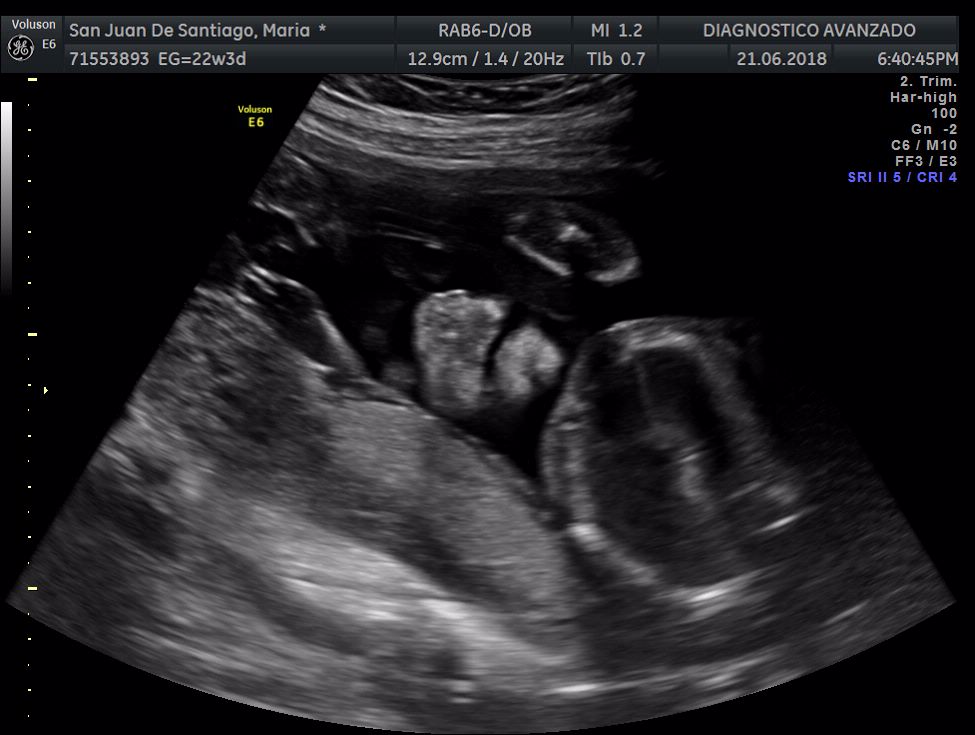

¡Hola a todos! Hoy hemos ido a hacer la tradicional ecografía 3D de la niña, os dejamos todo el material (aunque es un poco demasiado).